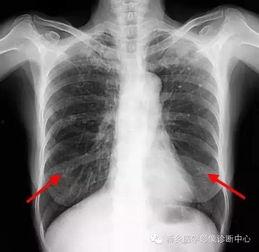

胸片检查是诊断肺部疾病的重要手段。通过观察肺部影像,医生可以初步判断患者是否患有肺炎、肺结核、肺癌等疾病。

2. 心脏疾病诊断

胸片检查还可以用于诊断心脏疾病,如心包积液、心脏增大等。